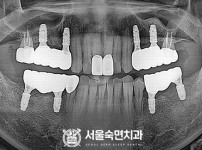

임플란트-전후사진2